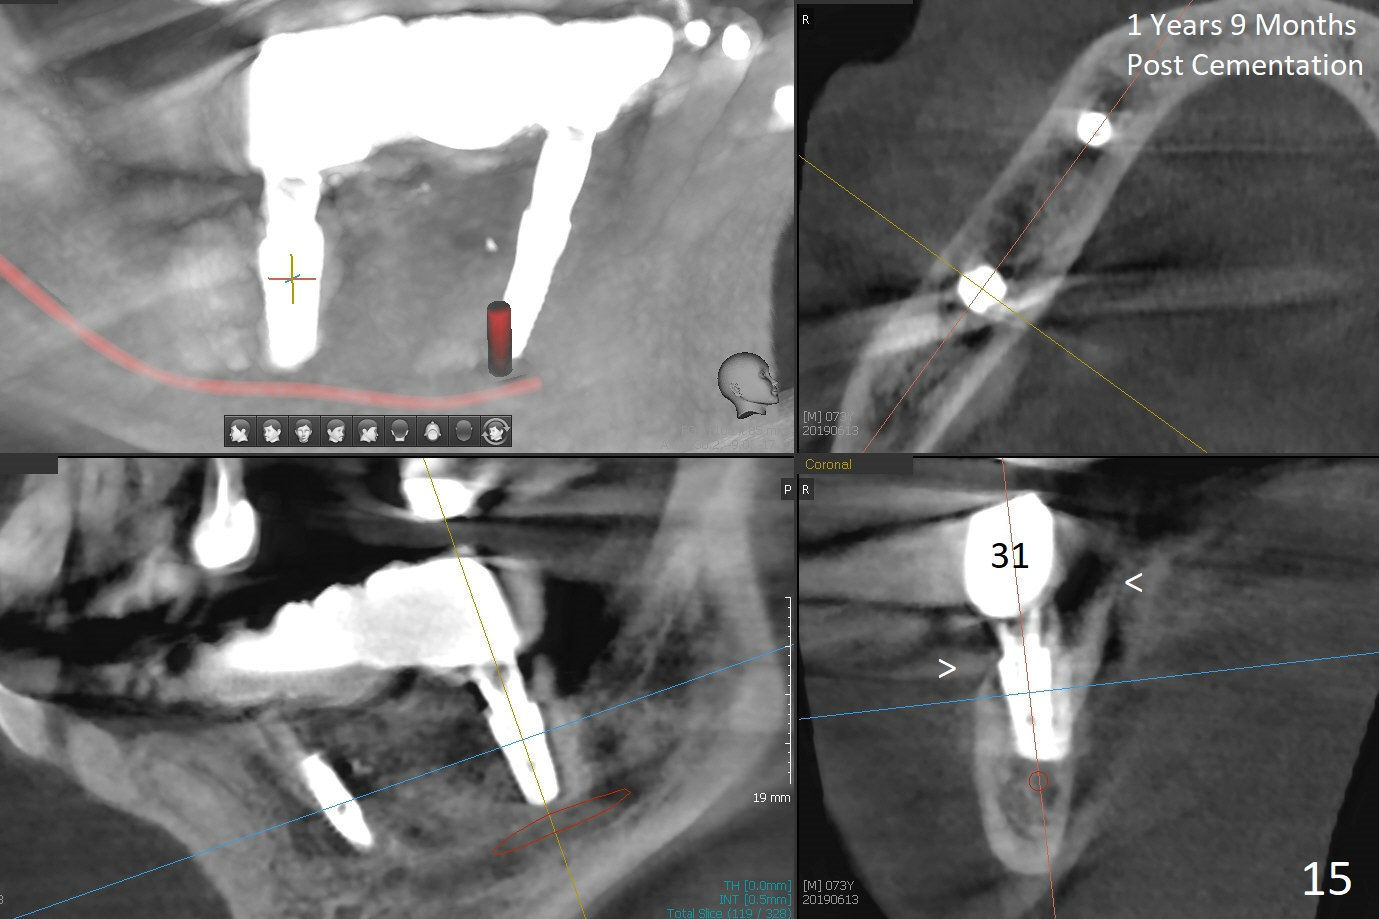

The patient will return in two weeks (total 2 months postop). The abutment at #29 will be changed to a longer one (3.9x7(6) mm). Provisional FPD will be fabricated with an emphasis to push the surrounding (especially lingual) gingiva away from the abutments, most likely using gauze as gingival retraction cord. The crown at #2 will be trimmed to have clearance. Fig.13 is taken 3 months post cementation. CBCT taken 1 year 9 months post cementation shows the uneven buccal (B) and lingual crests (Fig.14,15 arrowheads).